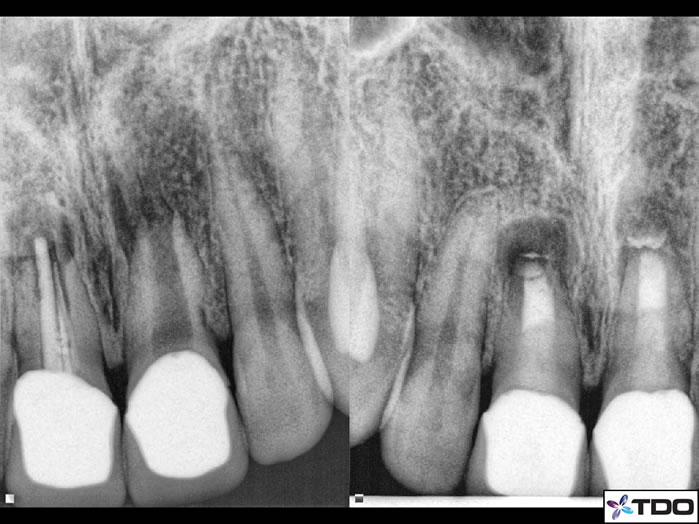

Figure 5: This case was just finished by Dr. Sherman. The pre-op shows wide open apices with tooth #8 having received inadequate original endodontic treatment. Tooth #9 is necrotic with incomplete apical formation. MTA is packed in the apical 4mm and a bonded fiber post over the top of the MTA.

Figure 6: I completed this case a couple years ago. the pre-op with over instrumented and over filled RCT in the upper left. The upper right is with all materials removed. The lower left is with MTA in the apical section. And the lower right is the completed case with bonded post/composite seal.